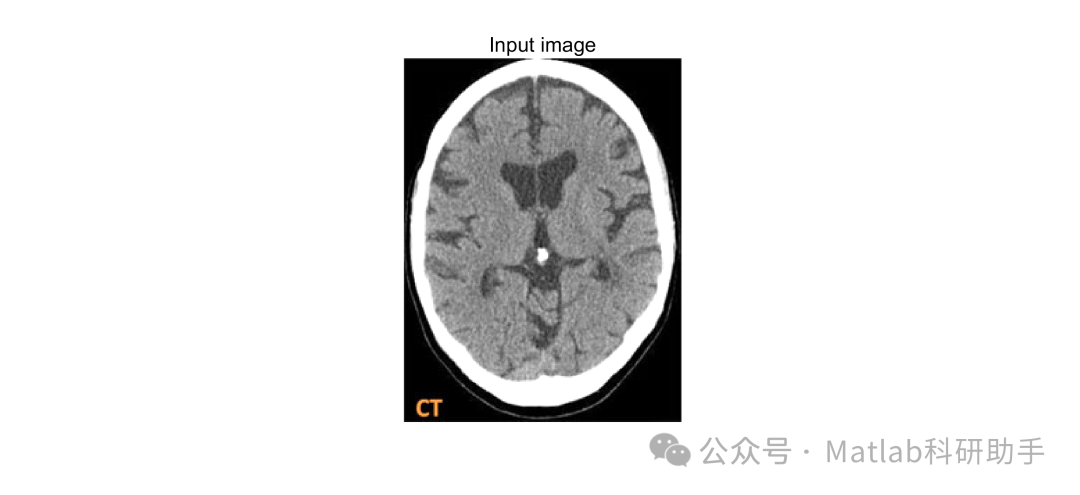

⛳️ 运行结果